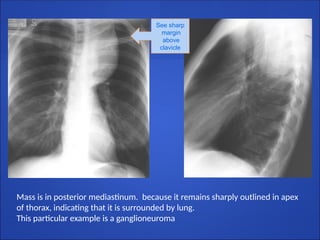

Cervicothoracic sign

●The anterior mediastinum ends at the level of the

clavicles.

●The posterior mediastinum extends much higher.

●Therefore

● any mass that remains sharply outlined in the

apex of the thorax must be posterior and

entirely within the chest, and

● any mass that disappears at the clavicles must

be anterior and extends into neck

See sharp

margin

above

clavicle

Mass is in posterior mediastinum. because it remains sharply outlined in apex

of thorax, indicating that it is surrounded by lung.

This particular example is a ganglioneuroma